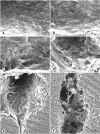

Leakiness of blood vessels in tumors may contribute to disease progression and is key to certain forms of cancer therapy, but the structural basis of the leakiness is unclear. We sought to determine whether endothelial gaps or transcellular holes, similar to those found in leaky vessels in inflammation, could explain the leakiness of tumor vessels. Blood vessels in MCa-IV mouse mammary carcinomas, which are known to be unusually leaky (functional pore size 1.2-2 microm), were compared to vessels in three less leaky tumors and normal mammary glands. Vessels were identified by their binding of intravascularly injected fluorescent cationic liposomes and Lycopersicon esculentum lectin and by CD31 (PECAM) immunoreactivity. The luminal surface of vessels in all four tumors had a defective endothelial monolayer as revealed by scanning electron microscopy. In MCa-IV tumors, 14% of the vessel surface was lined by poorly connected, overlapping cells. The most superficial lining cells, like endothelial cells, had CD31 immunoreactivity and fenestrae with diaphragms, but they had a branched phenotype with cytoplasmic projections as long as 50 microm. Some branched cells were separated by intercellular openings (mean diameter 1.7 microm; range, 0.3-4.7 microm). Transcellular holes (mean diameter 0.6 microm) were also present but were only 8% as numerous as intercellular openings. Some CD31-positive cells protruded into the vessel lumen; others sprouted into perivascular tumor tissue. Tumors in RIP-Tag2 mice had, in addition, tumor cell-lined lakes of extravasated erythrocytes. We conclude that some tumor vessels have a defective cellular lining composed of disorganized, loosely connected, branched, overlapping or sprouting endothelial cells. Openings between these cells contribute to tumor vessel leakiness and may permit access of macromolecular therapeutic agents to tumor cells.